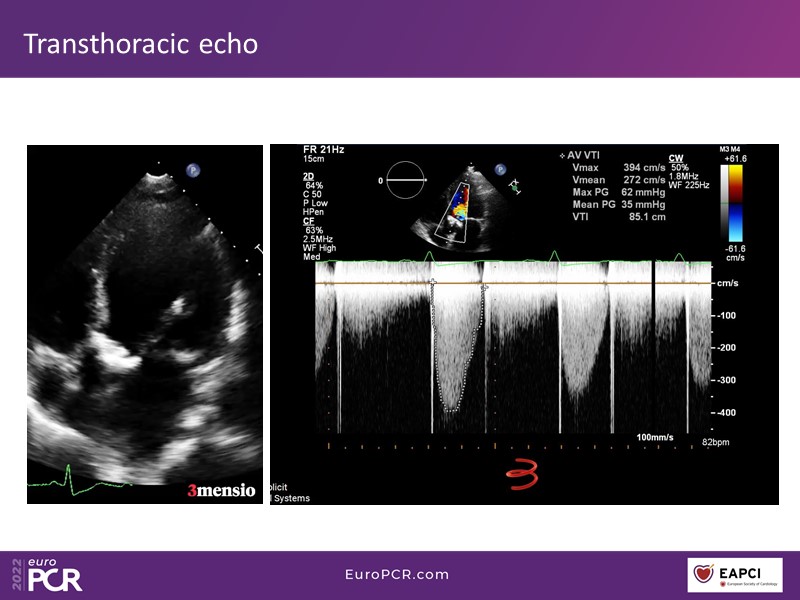

Through the presentation of real-life clinical cases, this session will allow you to discover the use of ALLEGRA for valve-in-valve TAVI, understand the management of coronary artery disease in TAVI patients, better detect when and how to protect coronary arteries during TAVI, or even learn how to perform commissural alignment with ALLEGRA.

- To understand the management of coronary artery disease in patients undergoing TAVI